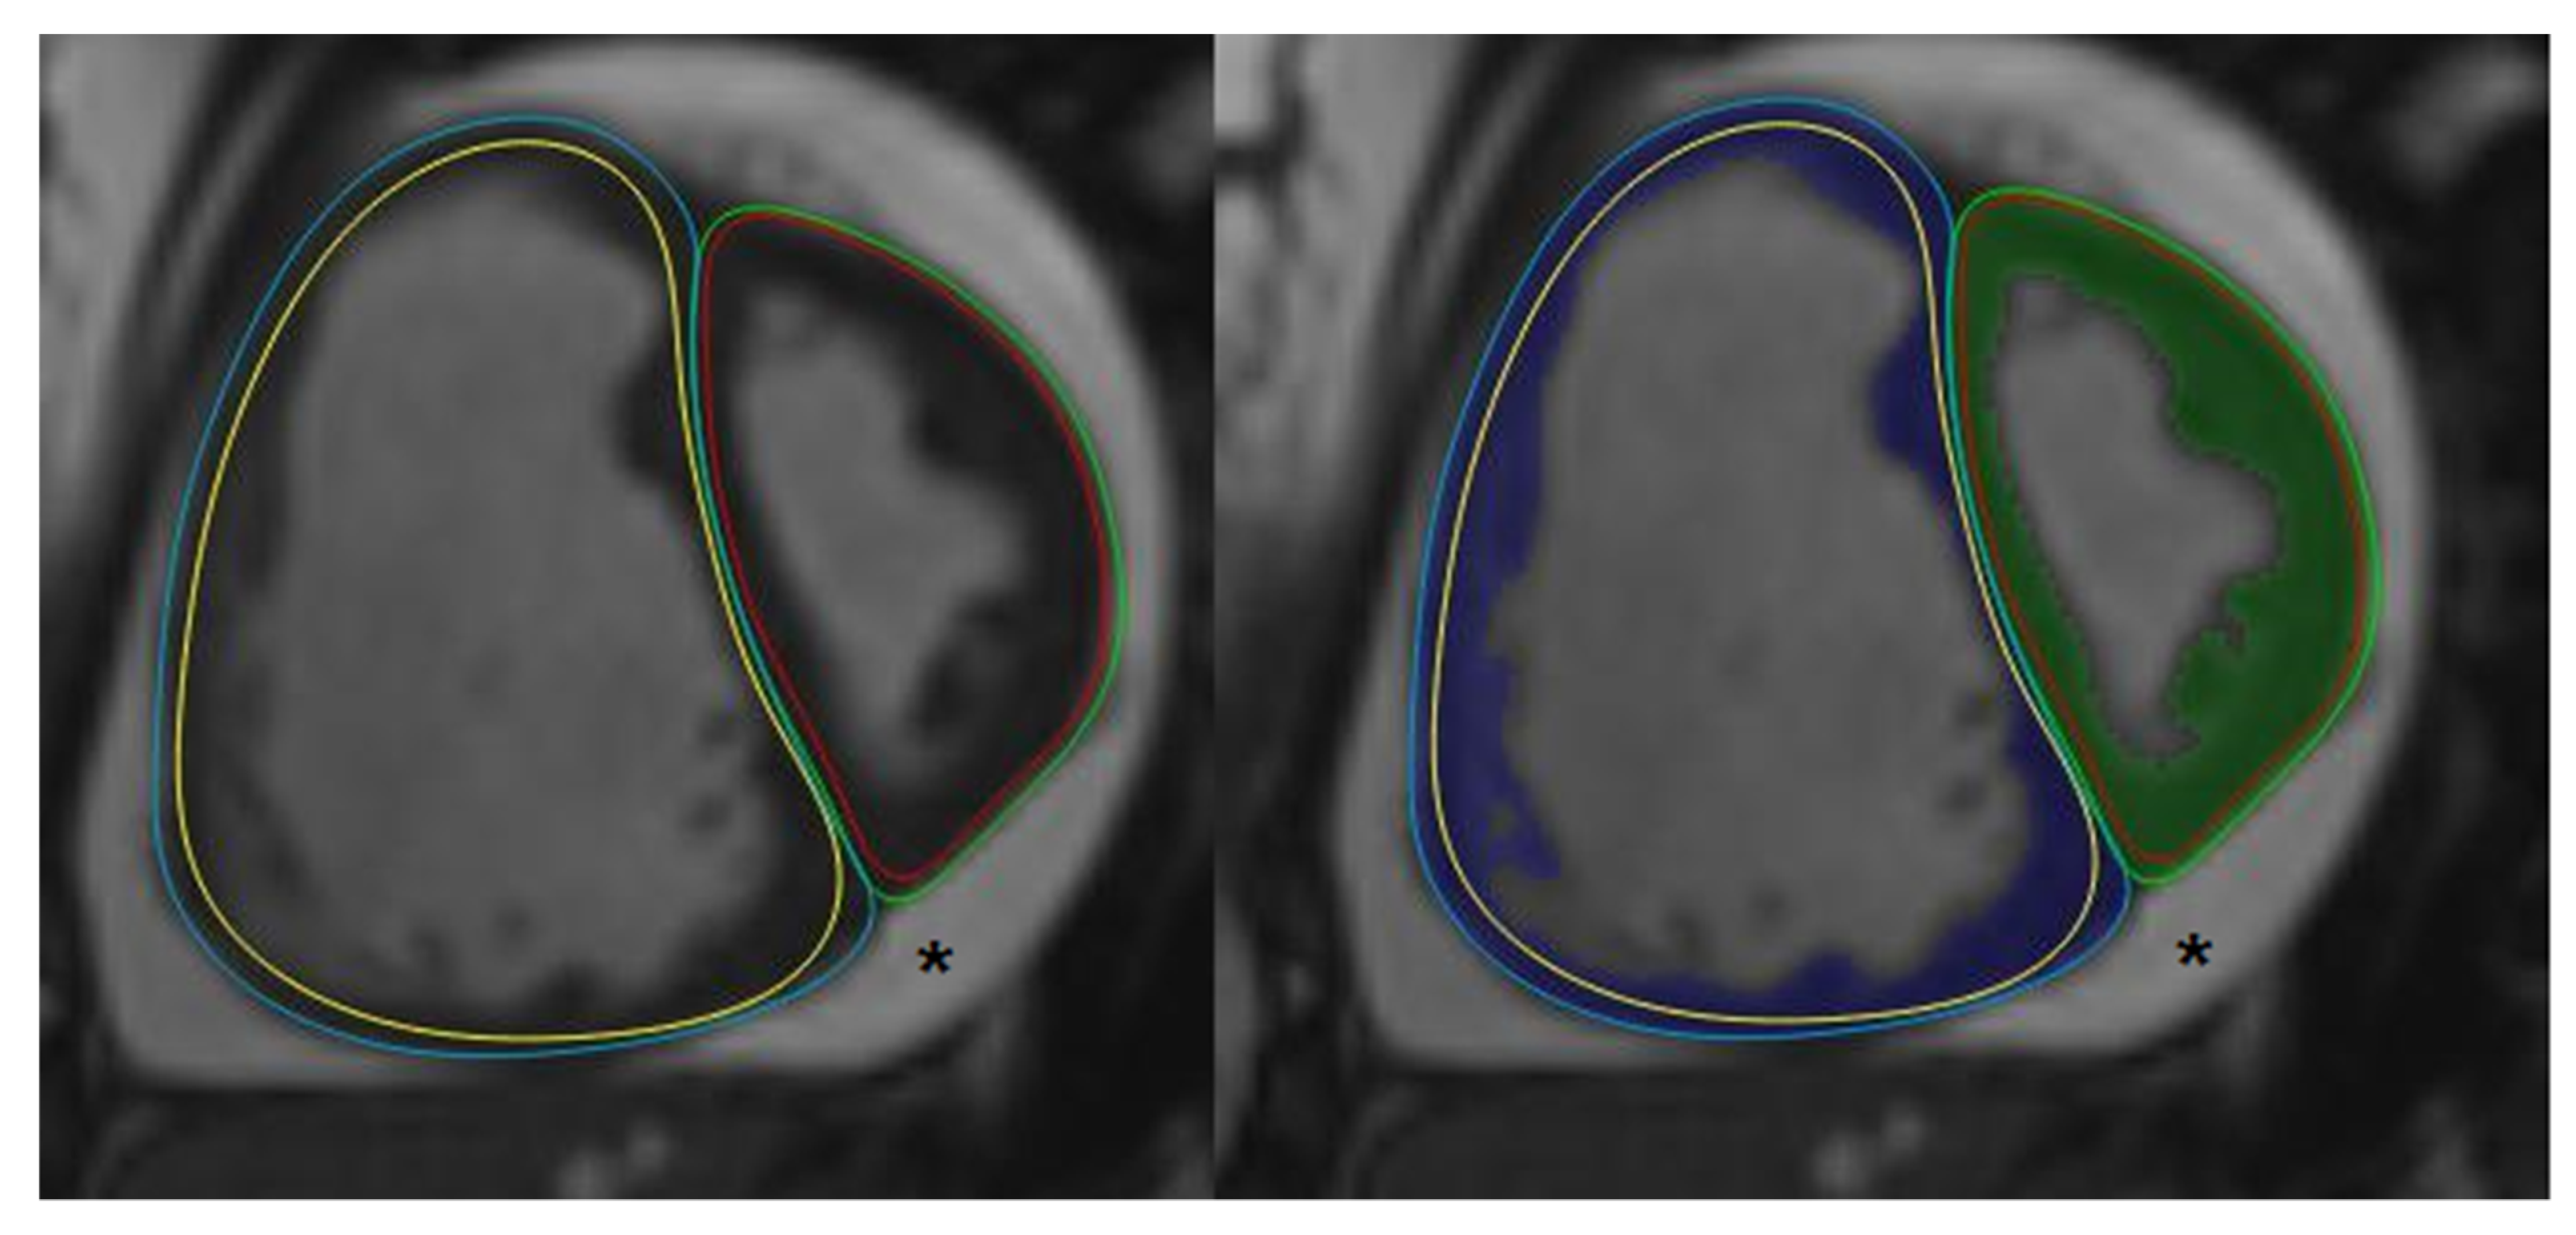

2.2. Cardiac Magnetic Resonance

2.3. Post-Processing